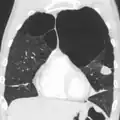

A CT scan is not routinely used except for the exclusion of bronchiectasis.[5] Pulse oximetry measurement of peripheral oxygen saturation is recommended in people with clinical signs of respiratory failure or right heart failure.[5] An analysis of arterial blood is recommended in those with a peripheral oxygen saturation of 92% or less to determine actual blood oxygen level and assess for high levels of carbon dioxide in the blood, which may have therapeutic implications such as need for non-invasive ventilation or oxygen supplementation.[10] WHO recommends that all those diagnosed with COPD be screened for alpha-1 antitrypsin deficiency.[40]

Very severe emphysema with lung cancer on the left (CT scan)